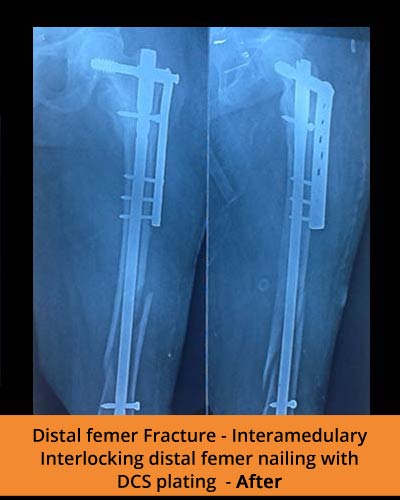

🩺 Fracture management and trauma care

At TPN Hospitals — the top orthopaedic hospital in Erode — our specialists use advanced methods to perform limb lengthening, correct deformities, and treat complex fractures with precision and care

Addressing infected non-union of long bones, osteomyelitis, and polytrauma cases with specialized care.